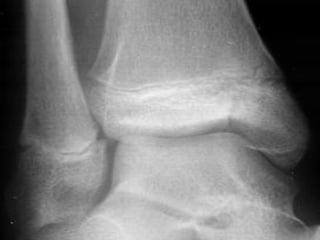

CLASIFICACIÓN PARA LAS  EPIFISIOLISTESIS SALTER HARRIS